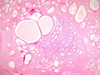

CASO N° 3 (Dr. Abel e Dr. Delgado)

Paciente do gênero masculino, 21 anos de idade, apresenta uma lesão no palato duro.